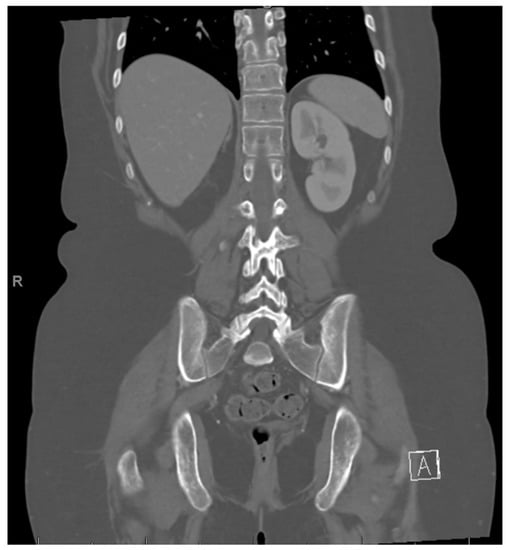

She completed 2 more cycles of chemotherapy and then proceeded with a right nephrectomy and retroperitoneal lymph node sampling. Pathology was consistent with excellent treatment response and no evidence of viable tumor in either the nephrectomy or the seven resected paracaval and aortocaval lymph nodes. After surgical clearance, she resumed chemotherapy. However, carboplatin 400 mg/m2 on day 1 was substituted for cisplatin due to reduction of kidney function. Cycle 5 day 15 of chemotherapy was delayed for thrombocytopenia, and day 15 was omitted from cycle 6 again due to thrombocytopenia. Towards the end of treatment, she required prolonged antibiotic therapy for multiple infections. She was diagnosed with enteropathogenic E. coli gastroenteritis and E. coli urinary tract infection and was treated with IV cefepime. She had increased abdominal tenderness and was diagnosed with typhlitis based on CT abdomen. Antibiotics were escalated to IV meropenem. During the same hospitalization, blood cultures were positive for Candida tropicalis, and Staphylococcus epidermis. IV vancomycin and IV caspofungin were added to her treatment. She completed a course of oral linezolid and oral fluconazole to complete a course of 14 days. Her blood counts recovered, and she was able to complete a total of 6 cycles of chemotherapy, with end of therapy PET/CT negative for any FDG-avidity and no evidence of residual tumor, as well as abdomen MRI negative for disease (Figure 6).

Figure 6. Post right nephrectomy.